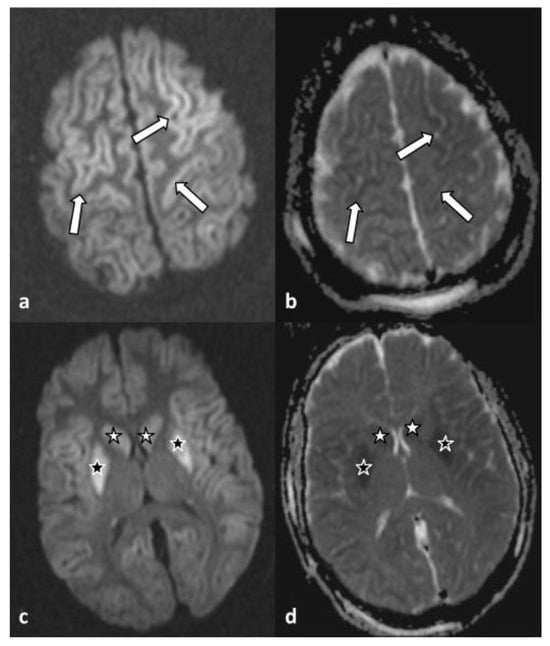

A habit history of frequent spring water consumption reported by her closest contact, along with the reports of endemic tropical diseases on the island of her residency, raised the suspicion of leptospirosis infection, although the serological test of the first sample was negative. Based on that, eight days later, a second blood sample revealed positive IgM against Leptospira (immunochromatographic assay) and confirmed the diagnosis. Targeted therapy with 2 g of ceftriaxone intravenously, which was started empirically on the second day based on high grade of clinical suspicion was completed. On the 5th day, an attempt of analgosedation discontinuation was interrupted as the patient presented multiple episodes of myoclonus, exophoria, and impaired level of consciousness (GCS 6/15). A brain magnetic resonance imaging (MRI) revealed findings indicative of cytotoxic edema in the context of global hypoxic ischemic injury (Figure 1) of the caudate (white asterisk) and the lentiform (black asterisk) nuclei, bilaterally. On the corresponding apparent diffusion coefficient map (d), the same areas appeared hypointense.

Figure 1. Axial diffusion-weighted imaging (a) and apparent diffusion coefficient map (b) at the level of the convexity, showing increased and decreased signal intensity of the cerebral cortex along both frontal lobes (arrows), respectively. Axial diffusion-weighted imaging (c) at the level of basal ganglia reveals symmetrical hyperintensity of the caudate (white asterisk) and lentiform (black asterisk) nuclei, bilaterally. On the corresponding apparent diffusion coefficient map (d), the same areas appear hypointense.